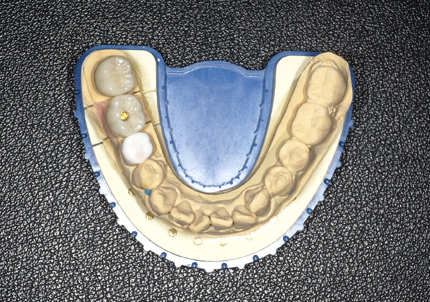

12.左下6・7番埋入サージカルガイド作製

13.サージカルガイドによる埋入手術(2019年5月)

14.インプラント埋入

※ 初期固定35N/cm確認する

※ 埋入後の縫合は強さに十分注意する

17.シリンダーテック作製(2019年10月)

側方から見て形状の確認